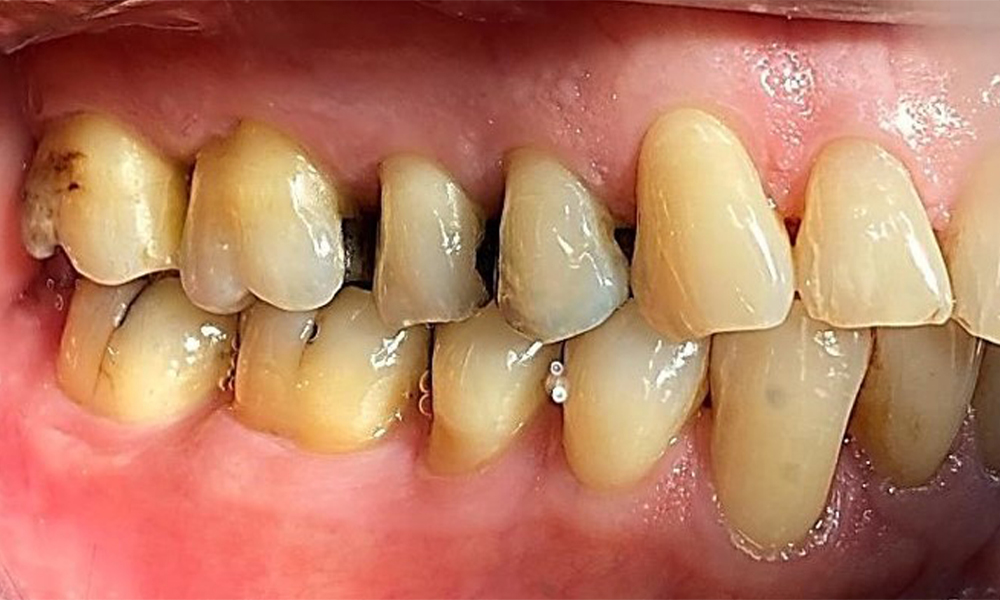

Right lateral view. Loss of the interdental papillae.

Fig. 3 Right lateral view. Loss of the interdental papillae. © Dr R. Krapf

Left lateral view including the recessions.

Fig. 4 Left lateral view including the recessions. © Dr R. Krapf

The patient has a full dentition with 28 teeth, which includes amalgam and composite fillings in the molar and premolar regions. There is a visible clinical marginal gap present on tooth 14. Tooth 27 has an adequate gold inlay. There are also generalized attritions and abrasions. (Fig. 2, Fig. 3, Fig. 4, Fig. 5, Fig. 6)

The patient has stage II, grade B periodontitis (5). At 1 to 3 mm, the clinical probing depths were within the physiological range. Localized probing depths of 5 mm were observed on the mesiopalatal aspects on both 17 and 27. There are generalized recessions of 1–3 mm with partial loss of the interdental papillae (Fig. 2, Fig. 3, Fig. 4)